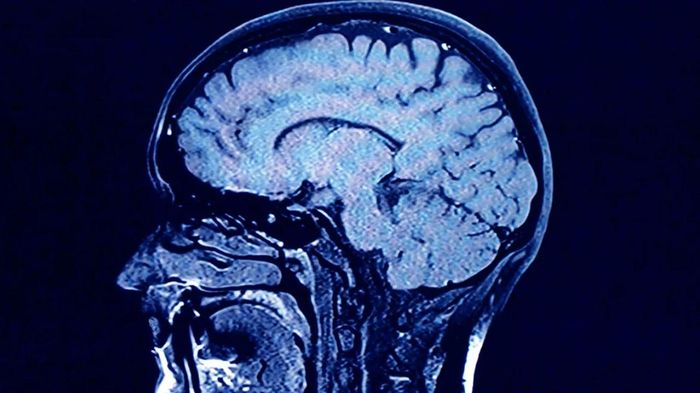

Các nhà nghiên cứu đang khám phá về quá trình lão hóa của não bộ con người, đồng thời những cách thức để bảo vệ sức khỏe não bộ, bao gồm việc tập thể dục, không hút thuốc, học ngôn ngữ mới và chơi nhạc cụ.

Các nhà nghiên cứu phát hiện ra rằng cả yếu tố di truyền và lối sống đều có thể ảnh hưởng đến quá trình lão hóa của não bộ. Ảnh: Getty Images